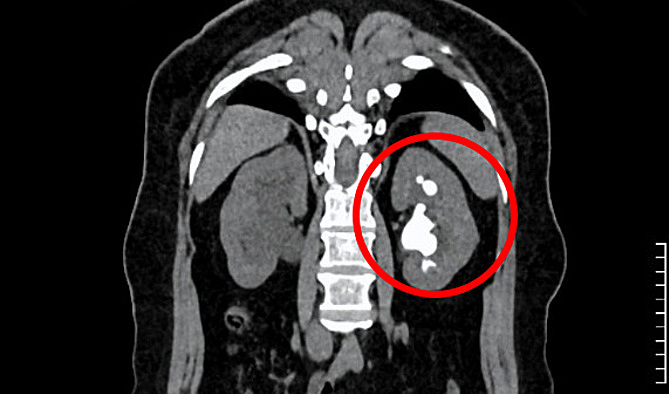

Kết quả khám tại Bệnh viện Đa khoa Tâm Anh TP HCM ghi nhận người bệnh có sỏi ở đoạn trên niệu quản phải, kích thước khoảng 8×10 mm. Thận trái cũng có sỏi kích thước 24×42 mm cùng nhiều sỏi nhỏ ở đài thận trên. ThS.BS Nguyễn Tân Cương, Phó khoa Tiết niệu, Trung tâm Tiết niệu – Thận học – Nam khoa, cho biết sỏi thận trái có hình dạng san hô lấp đầy các đài thận, nguy cơ nhiễm khuẩn và tổn thương thận âm thầm, người bệnh cần phẫu thuật sớm.

Sỏi san hô cứng, kích thước lớn (màu trắng trong hình tròn đỏ) ở thận trái gây đau đớn cho người bệnh. Ảnh: Bệnh viện Đa khoa Tâm Anh